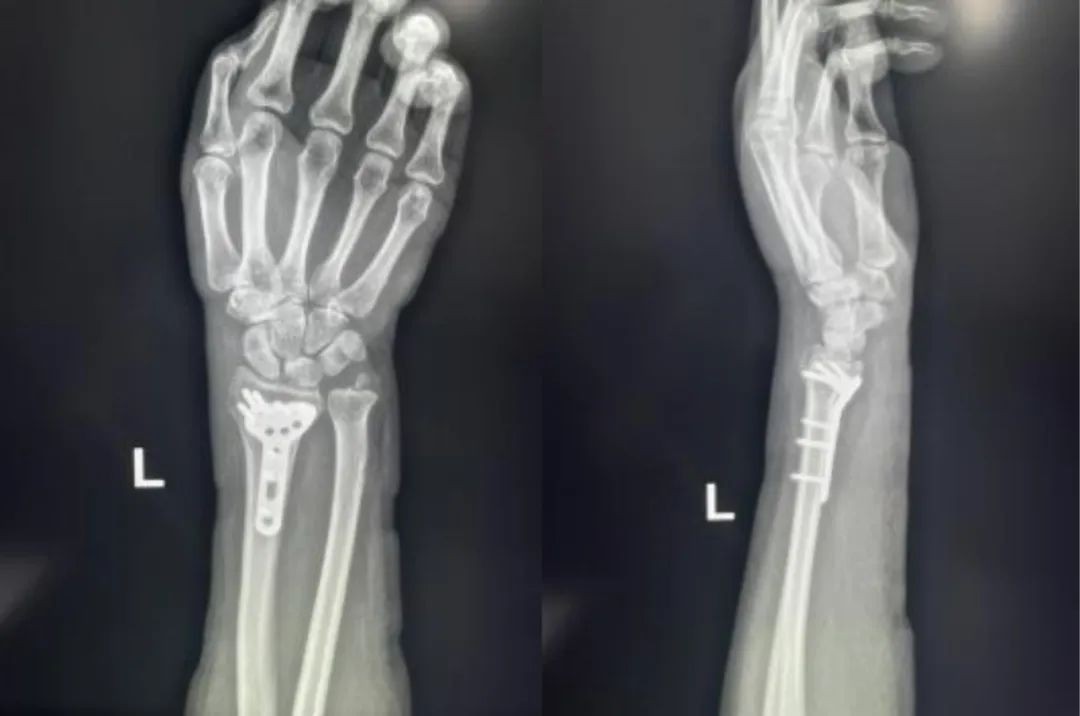

Случай ③